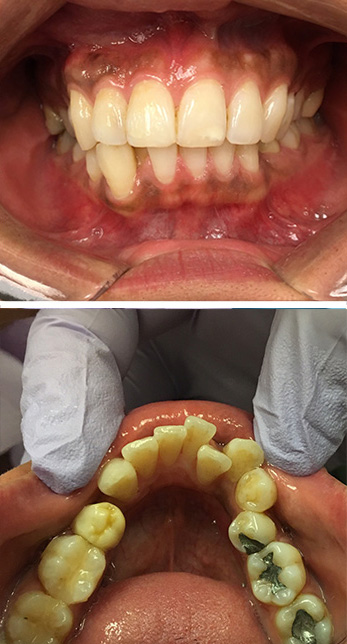

Invisalign

Family Dentist in Amityville

Before

Amityville Emergency Dentist

After